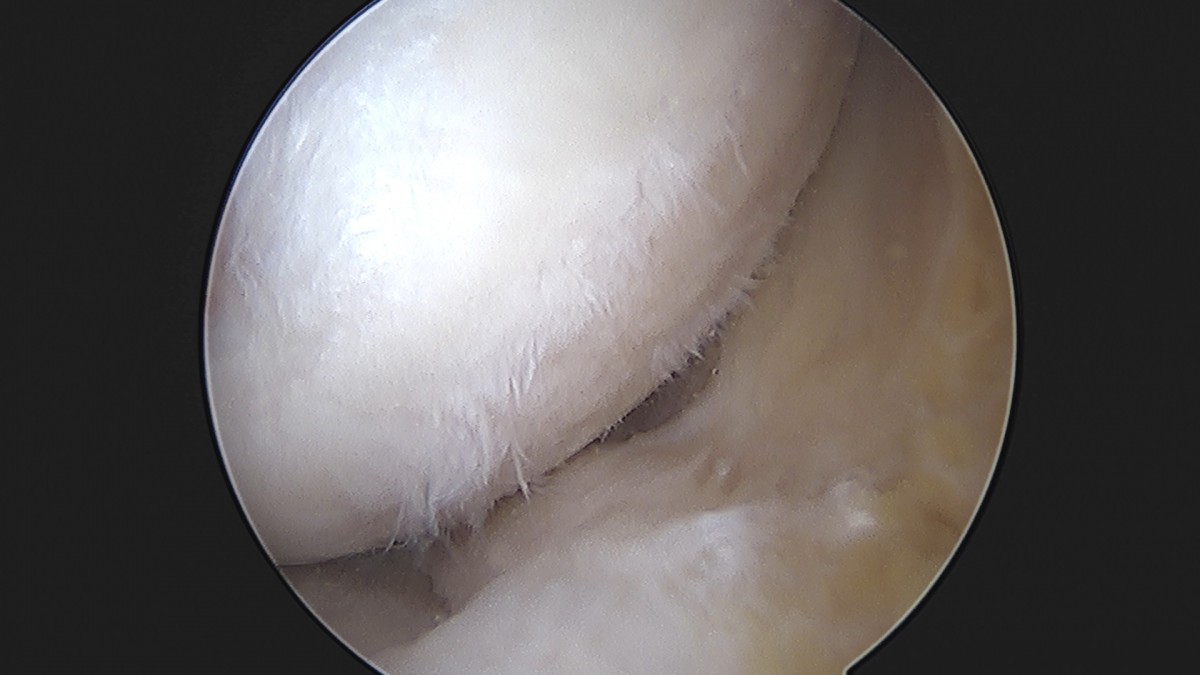

이재상원장님 무릎 반월상 연골판 절제술 장영O 환자

작성자 최고관리자 댓글 0건 조회 369회 작성일 25-09-16 16:02

dae765e4d9ac96aee867c9d6292d8784_1758006135_5178.jpg